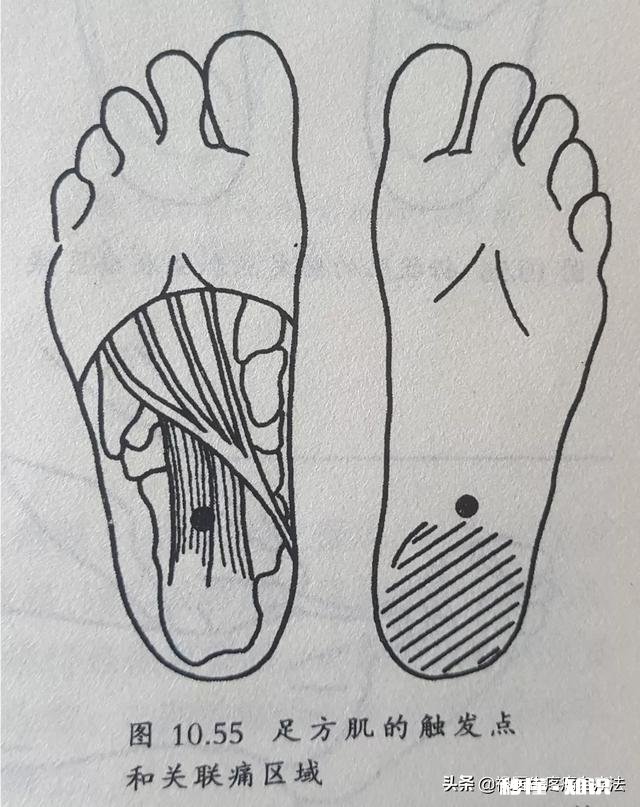

比目鱼肌损伤后会引起小腿后面、跟腱及足跟底部疼痛 。它是足跟底部疼痛的主要原因 。足底的足方肌损伤后会引起跟骨底部的疼痛,经常会被医生诊断为足底筋膜炎 。

文章插图